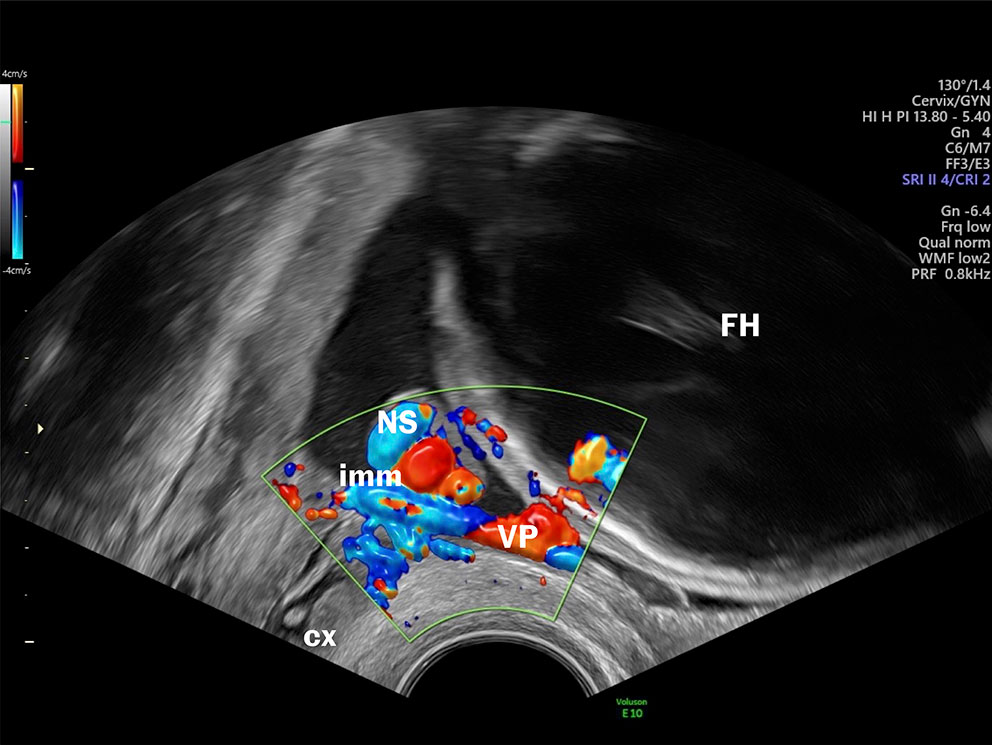

Although diagnosing vasa previa and velamentous vessels via ultrasound has been possible since the late 1980s, the routine examination in Norway does not include confirming or ruling out vasa previa. Transvaginal ultrasound has high sensitivity and specificity for diagnosing vasa previa (13), and false-positive and false-negative findings are rare. In addition, the examination is inexpensive, entails little patient discomfort, poses no risk to the fetus and is quick to perform (a few minutes) (Figure 1) (see the video at tidsskriftet.no).

imm=internal cervical os, VP=vasa previa, NS=umbilical cord, cx=cervix, FH=fetal head